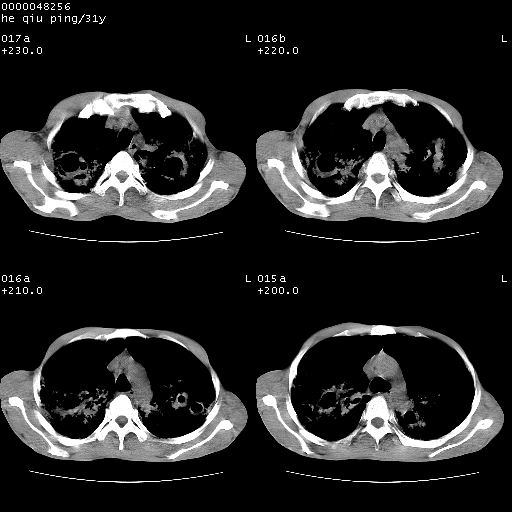

标题: CT13402:M,31Y。肺结核伴空洞形成?

咳嗽半月余,消瘦体质,呼吸音弱。无其他病史。cr:肺转移瘤待。

双侧弥漫性病变,双上叶尖后段、下叶北段见多个空洞,多见于结核感染。右中叶及双下叶斑片状,结节状影,考虑为肉芽肿形成及支气管播散。但由于患者消瘦体质,抵抗力低下,若继发感染,如金葡菌肺炎也有可能。

考虑为:两肺结核伴多发空洞形成、支气管播散。

两肺继发性结核伴多发空洞形成!不除外合并霉菌感染!